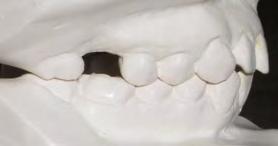

en paciente adulto tratado con extracciones de primeros molares permanentes. Reporte de caso

Dentista y Paciente 52 Sonriendo al futuro